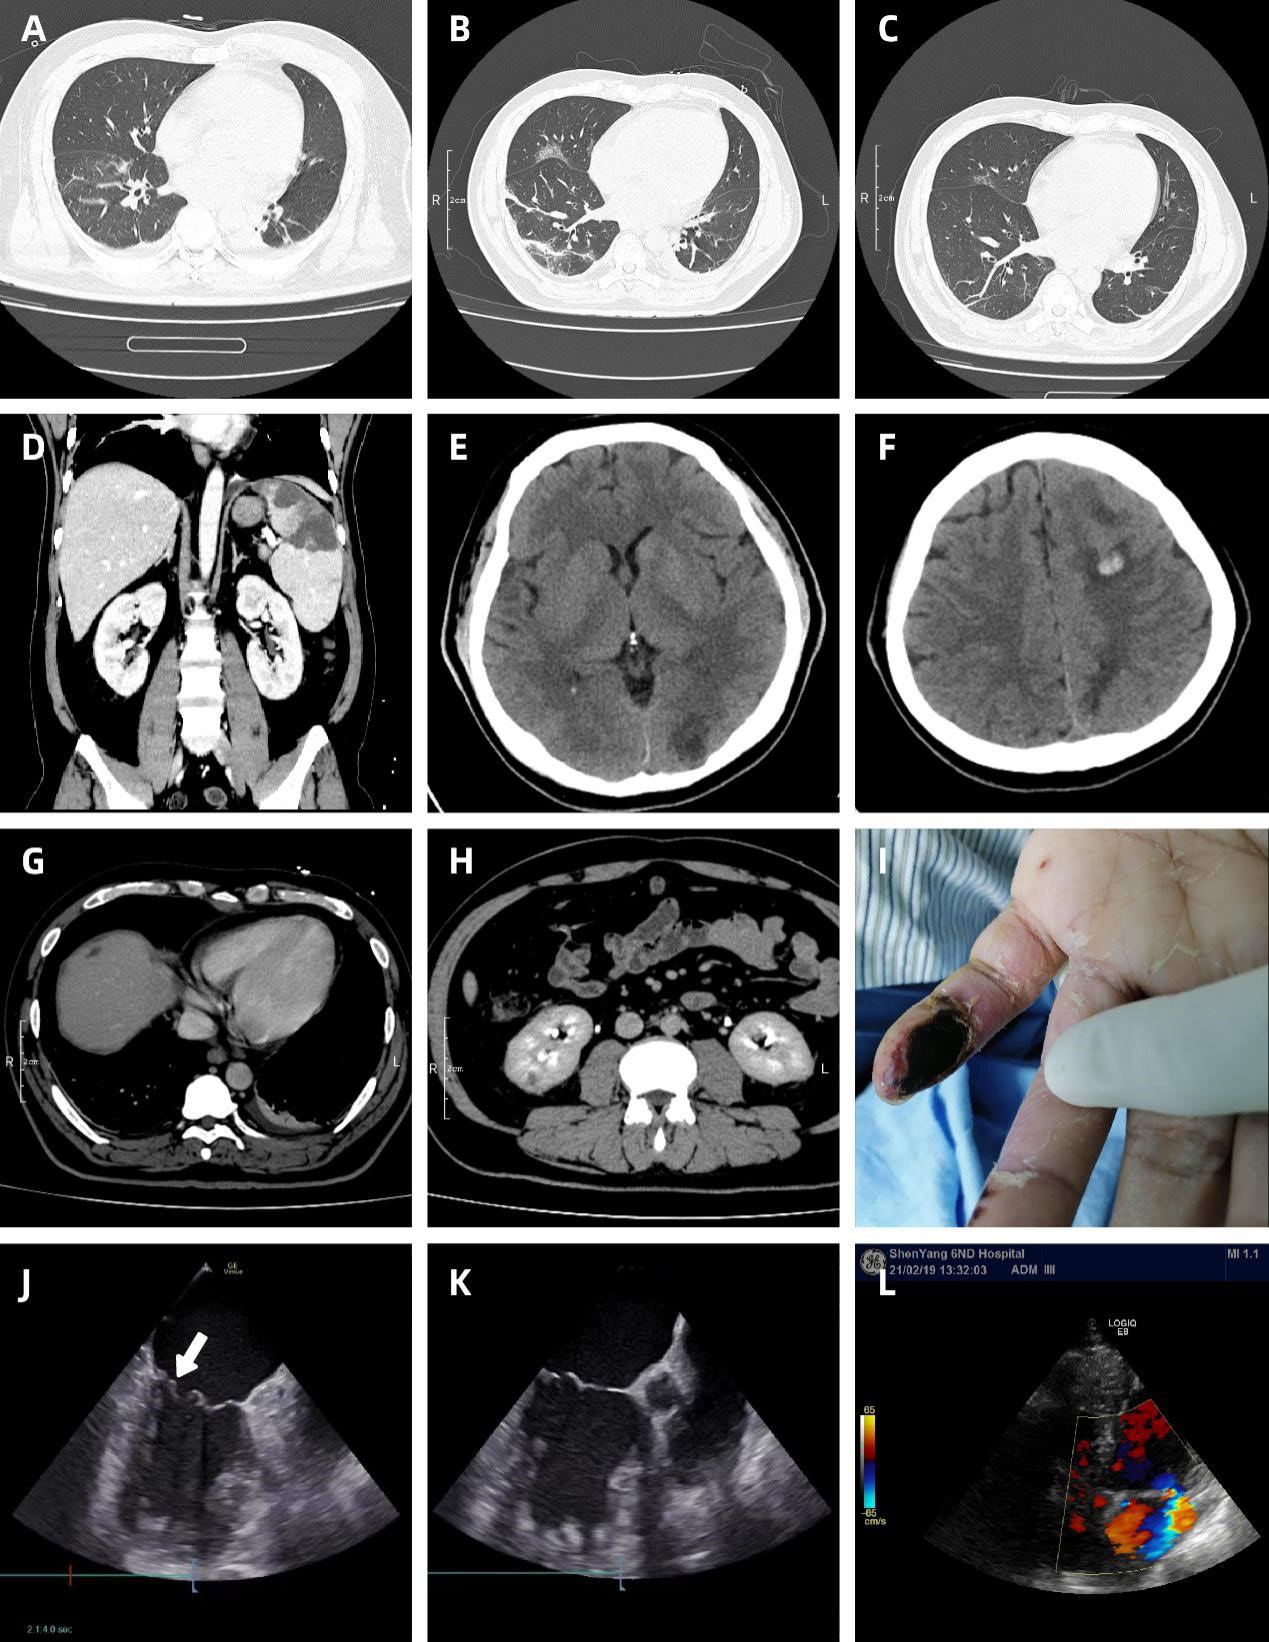

Figure 1: CT image. (A,B,C) The ground glass opacity of both lungs increased from a small amount to a patchy one with thickened blood vessels, and then to the inflammatory lesions. (D) Multiple splenic infarcts with the maximum diameter of 5.1 cm×3.6 cm and the tip pointed to splenic hilum. (E,F) Left parietal lobe hemorrhage and left occipital lobe infection with peripheral edema. (G) Low density necrosis in liver. (H) Low density small infarct in right kidney. (I) Necrosis of distal pinkie of left hand. Transoesophageal echocardiogram: (J) Vegetations in the heel of the left atrium near the posterior lobe of the mitral valve. (K) Mitral valve prolapse. Transthoracic echocardiogram: (L) Mitral valve regurgitation.

Day 2, transthoracic echocardiography (TTE) revealed mild mitral valve prolapse (Figure 1K) with regurgitation (Figure 1L) and left ventricular ejection fraction (LVEF) of 56.4%. CT revealed infectious foci in spleen (Figure 1D), kidney (Figure 1H), liver (Figure 1G) and intracranium with small hemorrhage in the left frontal lobe (Figure 1E). Blood cultures grew multidrug-resistant Staphylococcus aureus (MRSA). He was treated with daptomycin (0.8 g/d, 10 mg/kg/d) combined with fosfomycin sodium (16 g/d). Day 5, blood cultures were negative. Day 8, his senses of smell, taste, hearing and vision were weakened, and Osler's nodes appeared in the left little finger (Figure 1I). Repeat CT revealed progressive inflammation in both lungs (Figure 1B) and obvious edema around intracranial infarct focus (Figure 1F). Nucleic acid test result for SARS-CoV-2 was negative. Day 10, the patient experienced diarrhea, vomiting, headache, shortness of breath with SO2 88%, then was transferred to intensive care unit (ICU). Noninvasive assisted ventilation (FiO2 50%) was used to the patient whose SO2 increased to 94%–98%. Day 11, the patient was examined by transesophageal echocardiography (TEE) which found an additional isoechoic mass (1.2 cm × 1.2 cm × 0.8 cm) on the root of mitral valve (Figure 1J). A definitive diagnosis of IE was reached. Day 12, fosfomycin sodium was replaced by linezolid (1.2 g/d) due to the temperature was still beyond 39.0°C. Day 15, the temperature decreased to normal. CT revealed gradually absorbed pulmonary consolidation in both lungs (Figure 1C). Day 23, vegetation reduced to 1.2 cm × 0.3 cm × 0.5 cm. Day 25, linezolid was stopped while daptomycin continued. Day 43, daptomycin was stopped. Day 46, the patient was discharged.